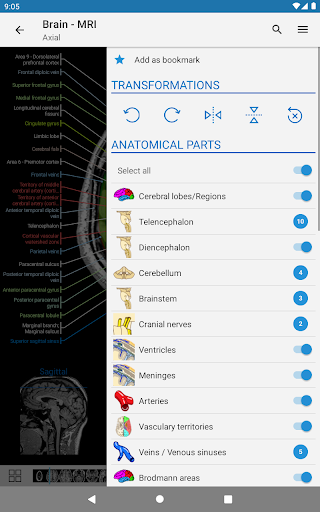

*Improved detail view of anatomical parts for easier identification in images of the current and other modules.

*Find your anatomical parts more easily thanks to the new, more intuitive and powerful search feature

- You can now hide structures one by one (new button inside the description popup) and display them again in the right menu